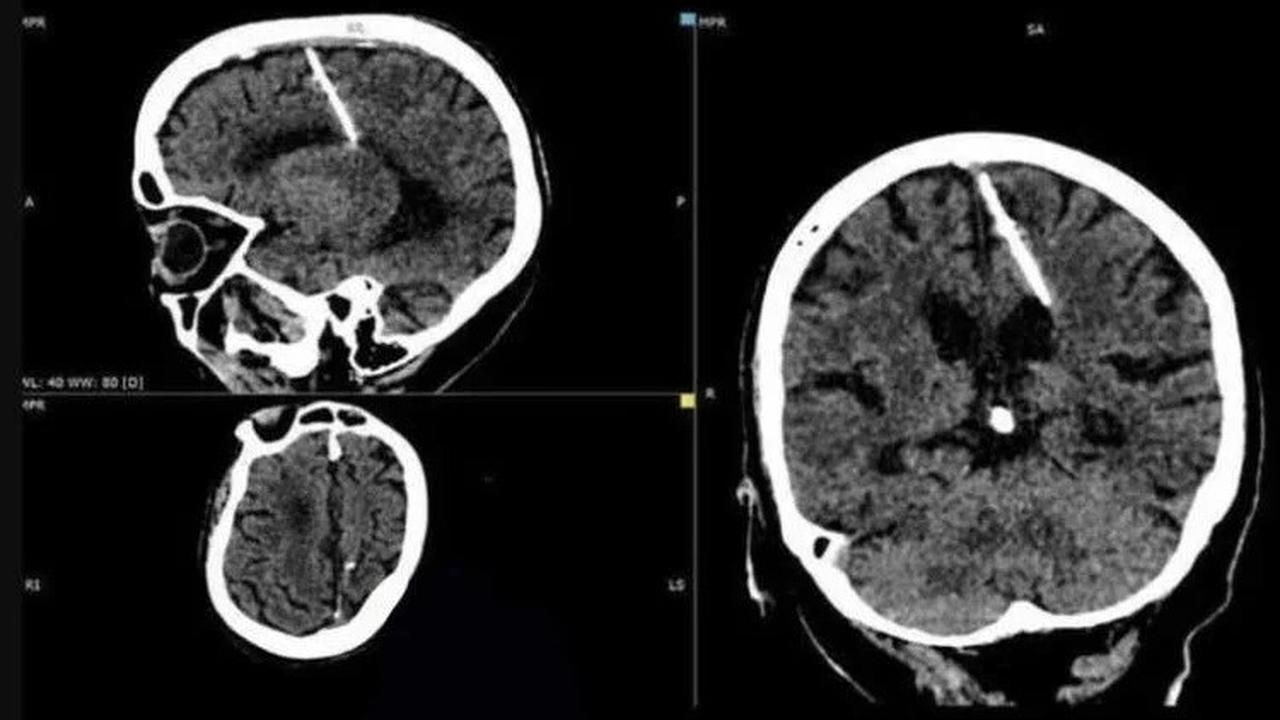

Liputan6.com, Jakarta Seorang wanita berusia 80 tahun dari wilayah Sakhalin, Rusia, baru-baru ini membuat penemuan yang mengejutkan setelah menjalani CT scan. Hasil pemeriksaan tersebut mengungkapkan adanya jarum logam berukuran 3 cm yang tertancap di sisi kiri otaknya.

Kementerian Kesehatan Sakhalin telah merilis foto hasil CT scan wanita tersebut, yang disertai dengan penjelasan yang membingungkan. Mempertimbangkan usia wanita tersebut, para dokter meyakini bahwa jarum tersebut dimasukkan ke dalam otaknya oleh orang tuanya sendiri segera setelah dia dilahirkan.

Para dokter yang merawatnya telah menyimpulkan bahwa intervensi bedah untuk mengangkat jarum logam tersebut akan membahayakan pasien, mengingat usianya yang sudah lanjut.

Oleh karena itu, mereka menyimpulkan bahwa jarum suntik tersebut tidak menimbulkan ancaman bagi kesehatannya, dan wanita tersebut akan melanjutkan hidupnya seperti biasa. Namun, dia akan tetap berada di bawah pengawasan ketat dokternya.